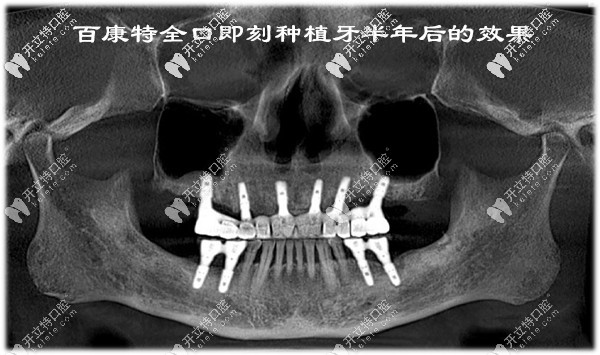

百康特全口即刻種植牙半年后的效果:

CBCT檢查顯示,上下頜植入的10顆百康特種植體都比較穩(wěn)定,顳下頜關(guān)節(jié)也無明顯異常。

百康特全口即刻種植牙半年后的效果